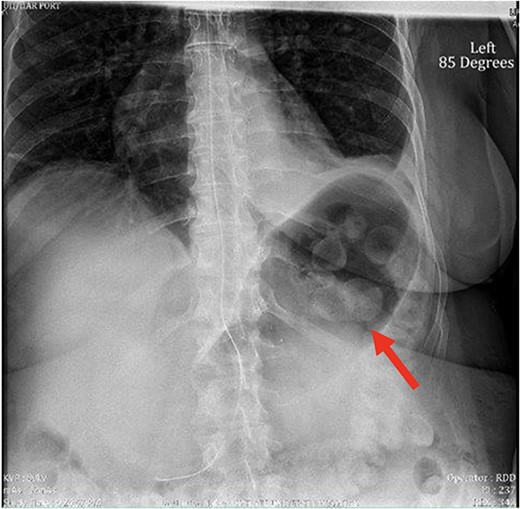

Despite the insertion of the NGT yielding 1500 cc output in 24 hours, the patient continued to experience severe abdominal pain. Urgent abdominal and pelvic computed tomography (CT) scans were taken, as seen in Figs 2–4. The CT scans showed gastric distension and the spleen positioned anteriorly in the right upper quadrant. Consequently, the decision was made to promptly bring the patient to the operating room for a diagnostic laparoscopy with plan to detorse the spleen.

CT of the abdomen and pelvis (sagittal slice) showing gastric distention and the spleen positioned anteriorly.

Our patient’s pre-existing conditions presented challenges in distinguishing between expected postoperative discomfort and potential complications following her recent adrenalectomy. This uncertainty, combined with a normal WBC count, absence of fever, and regular bowel function, initially led the medical team to attribute her pain to the recent surgery two days prior, delaying her diagnosis and potentially exacerbating her condition. Subsequent imaging became imperative, revealing a persistent large gastric bubble despite NGT decompression, and malposition of the spleen (Fig. 3). This prompted immediate preoperative measures to facilitate a diagnostic laparoscopy.